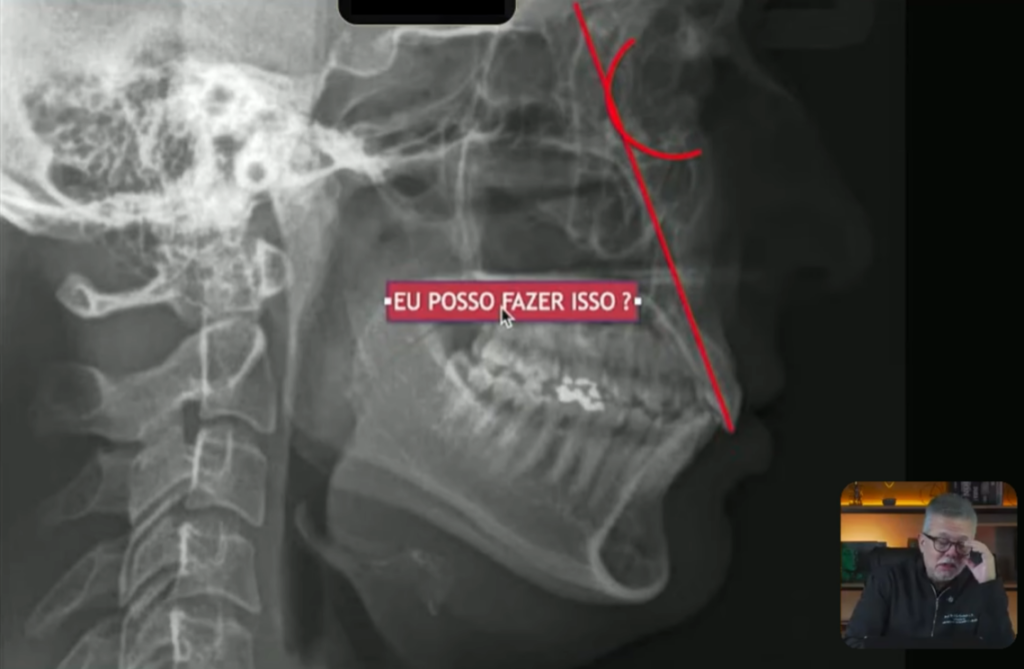

vamos imaginar que eu vou fazer o tratamento da classe 2, e essa paciente ela tem uma classe 2 unilateral:

Quando eu vou fazer o tratamento dessa classe 2, eles estão em uma posição ideal, eles estão bem posicionados, o superior ele está quase tangenciando a órbita, o incisivo superior está levemente lingualizado:

Esse inferior está quase bem posicionado,

só que deu para observar que tanto o superior quanto o inferior, o superior está levemente lingualizado e o inferior está levemente vestibularizado:

Só que quando eu olho para essa teleradiografia, eu posso deixar isso acontecer?

Eu tenho certeza agora que vocês vão falar assim, não professor, não pode, por quê?

Porque os incisivos superiores já estão lingualizados, se você retrair os incisivos, eles vão lingualizar mais ainda, você pode até retrair, mas você não pode deixar lingualizar.

Então nós teríamos que fazer aqui um negócio chamado torque vestibular